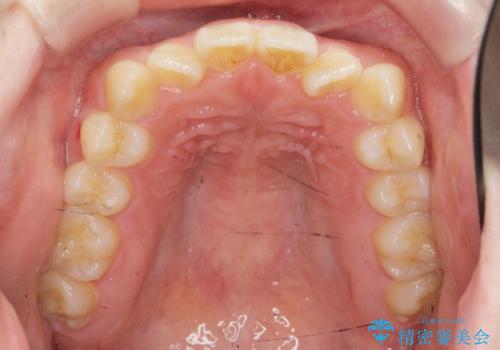

- ねじれの目立つ前歯を改善したいと、矯正治療を希望され来院されました。

インビザラインの不得意な上顎前歯のねじれの改善を、マウスピース矯正を行う前に前歯のみの部分ワイヤー矯正を行うことで治療期間の短期化を目指します。

上顎前歯のねじれはマウスピースで治りづらいため、マウスピース矯正の治療期間の長期化をきたしやすい歯列不正です。

マススピース矯正を始める前に、部分ワイヤー矯正を行うことで治療の短期間化・良好な仕上がりを達成することができました。